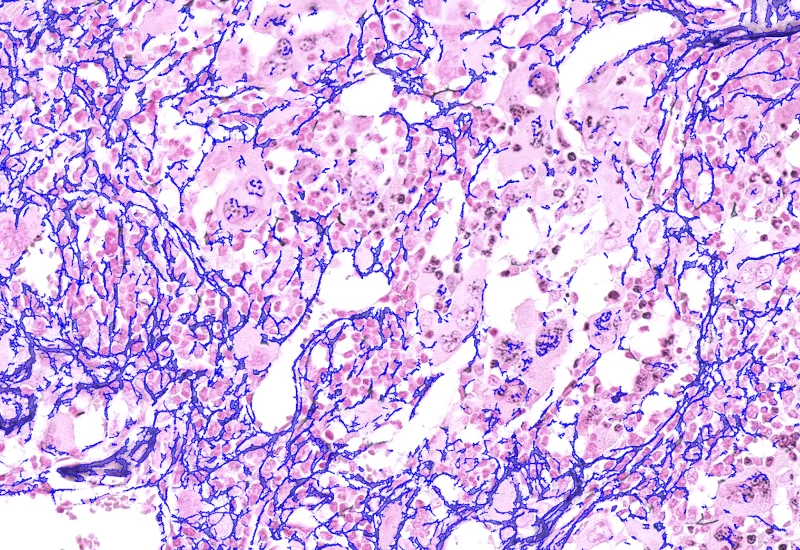

The Pulmo App segments nuclei and the metastructure components of the lung, including tissue, bronchioles, blood vessels, and alveoles. Each segmented metastructure is measured for up to 20 morphometric parameters.

App Category 3